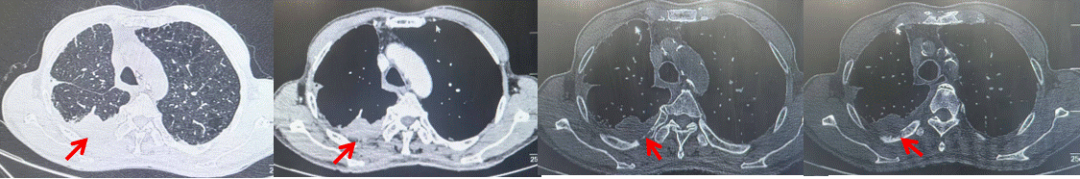

69岁男性,无糖尿病、高血压、心脏病等基础疾病,无吸烟、饮酒史,无肿瘤家族史。2023.06.07行胸部CT检查:右肺上叶胸膜下见肿物影,大小约33mm×22mm,边缘可见分叶,考虑恶性病变可能性大,双肺间质改变(如图1)。2023.06.14行“单孔胸腔镜下右肺上叶切除、肺门及纵隔淋巴结清扫、胸膜粘连松解术”;术后病理:(右肺上叶)腺癌(低分化,实体型占60%,不良腺体占40%),局灶伴神经内分泌标记表达(CD56、Syn),可见STAS及胸膜侵犯,未见确切神经侵犯及脉管内癌栓;(气管切缘)净;(淋巴结)未见转移癌0/26(2组0/2;4组0/6;7组0/2;对侧7组0/8;10组0/2;11组0/3;12组0/2;13组0/1)。术后分期pT2aN0M0 IB期,术后NGS基因检测:无驱动基因突变,PD-L1(22C3)TPS<1%。术后定期复查。

2024.11.19患者出现右侧胸痛,复查胸部CT检查示右侧胸膜肿物,大小约31mmX24mm,右侧4、5肋骨骨质破坏,考虑转移(如图2)。建议患者穿刺活检取病理明确诊断,患者拒绝,经MDT会诊后结合影像学表现及病史考虑为胸膜转移,肋骨转移,分期为rT0N0M1a IVA期,DFS仅仅17个月。2024.12.05起行信迪利单抗联合培美曲塞+卡铂方案治疗4周期,复查胸CT评效PR(如图3)。之后给予信迪利单抗+培美曲塞维持治疗6周期,期间复查CT评效PR(如图3)。目前信迪利单抗+培美曲塞维持治疗中,截止至目前PFS约为8个月,治疗期间未出现明显毒副反应。

图1:患者手术前(2023.06)胸部CT肺窗及纵隔窗

图2:患者胸膜及肋骨转移(2024.11)胸部CT肺窗、纵隔窗及骨窗

图3:患者免疫联合化疗治疗后胸部CT,(A、B)图展示信迪利单抗联合培美曲塞+卡铂治疗

4周期(2025.02)疗效,(C、D)图展示信迪利单抗+培美曲塞维持治疗6周期(2025.07)疗效